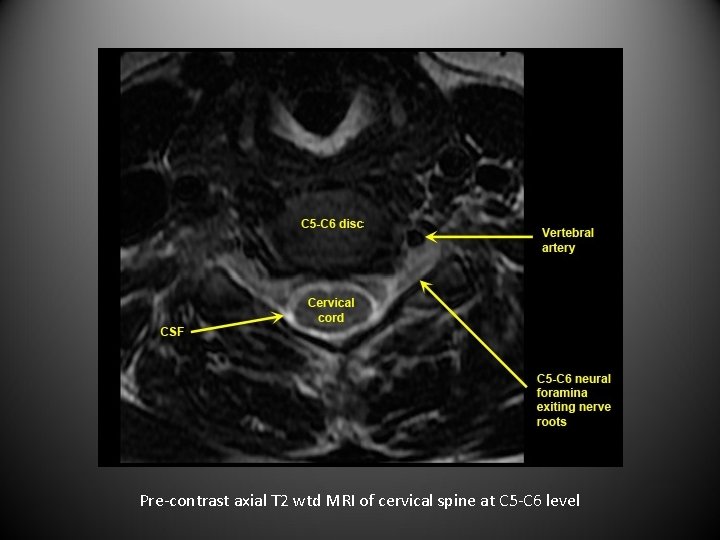

Pre-contrast axial T 2 wtd MRI of cervical spine at C 5 -C 6 level